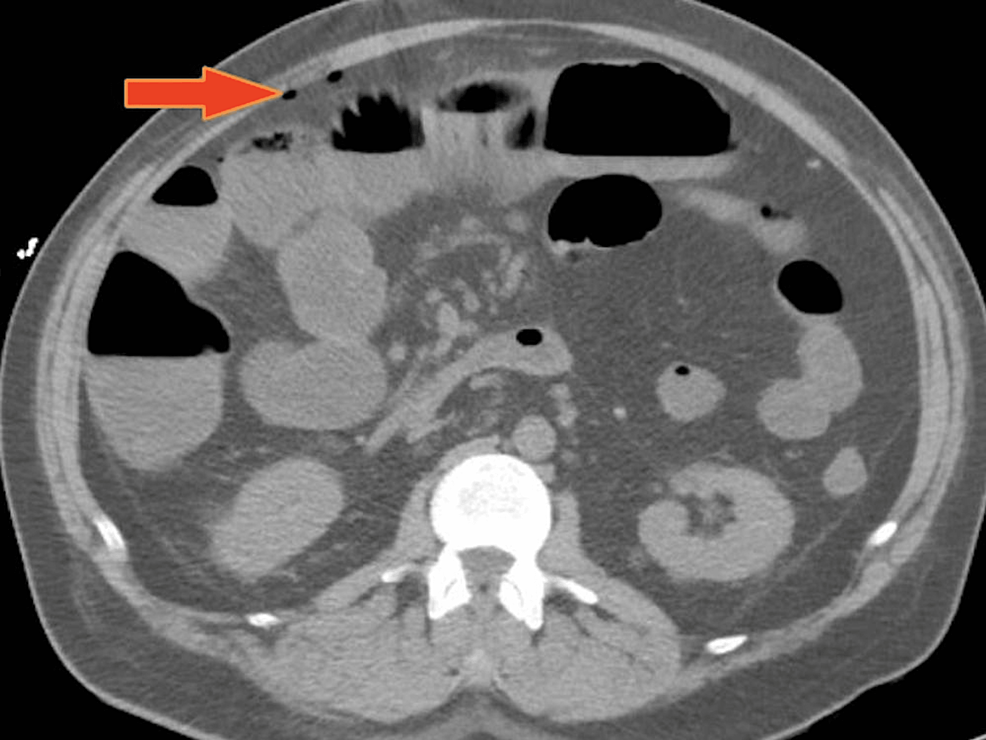

From www.cureus.com

Cureus OlmesartanInduced Ischemic Enteritis Complicated With Bowel Frozen Open Abdomen The term “open abdomen” (oa) refers to a surgically created defect in the abdominal wall that exposes abdominal. The open abdomen is an innovation that greatly improved surgical understanding of damage control, temporary abdominal closure,. With a frequency of 0.5% to 3% of all laparotomies, it is the inadvertent formation of. One of the damage control strategies used to avoid. Frozen Open Abdomen.